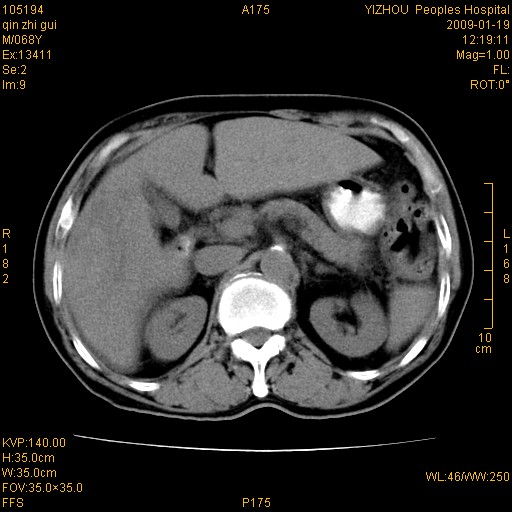

以下是引用随光逐影在2009-1-21 16:11:00的发言:[br]1)考虑肝右叶肝癌并肝静脉及门静脉瘤栓形成。2)肝硬化,少量腹水。3)胆囊炎。4)右侧少量胸腔积液。

病灶外缘凹凸不平,平扫低密度,增强动脉期有强化,门脉早显,静脉期及延期呈延迟强化,结合病史考虑右肝前叶巨块型肝癌可能性大,强化表现不除外胆管细胞癌